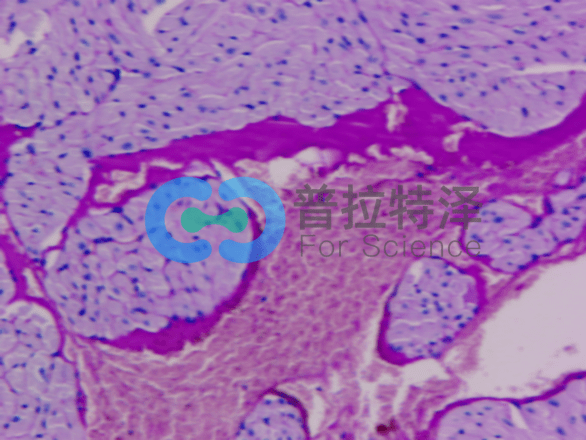

答:PAS染色,全稱周期性酸-希夫染色,是一種在組織學(xué)中廣泛應(yīng)用的染色方法。它的主要目的是檢測組織中的糖類物質(zhì)。在染色過程中,周期性酸發(fā)揮了關(guān)鍵作用,它能夠?qū)⑻穷愇镔|(zhì)中相鄰的兩個(gè)碳原子上的羥基氧化成醛基。隨后,希夫試劑與醛基發(fā)生反應(yīng),使糖類物質(zhì)呈現(xiàn)出獨(dú)特的紫紅色。這種染色方法不僅有助于我們觀察糖類的分布和形態(tài),還為研究糖類的生物功能提供了重要的線索。

→PAS染色主要用于檢測和鑒定組織或細(xì)胞內(nèi)的多糖和糖蛋白。

→PAS染色可以顯示細(xì)胞或組織中的糖原、粘附物、酸性黏多糖、肝細(xì)胞中的糖原顆粒等。

→染色原理:該染色方法利用過氧化物酶溶液和碘水處理后產(chǎn)生的醛團(tuán)與磷酸鉿反應(yīng),形成可見的紫紅色染色沉淀。